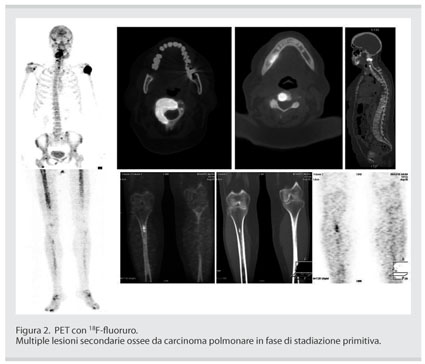

Le origini L’arco è un’arma antichissima (già usata dai cacciatori in età paleolitica) e diffusissima in tutte le sue varie forme;. Le fratture vertebrali lombari non hanno un’incidenza altissima come lesioni ossee, ma è importante sottolineare che le fratture del tratto dorsolombare rappresentano circa l’80% di tutte le lesioni ossee vertebrali Non è frequente vedere questa condizione patologica in centri privati di fisioterapia, perché le fratture vertebrali lombari possono avere conseguenze molto gravi, come. Questa consente quindi anche il trattamento delle lesioni ossee prima non possibili Gli esprimenti nel ratto prima Fig 2 Fig 3 e i trattamenti eseguiti su pazienti affetti da localizzazione ossee Fig 4 Fig 5 Fig 6 hanno permesso già di ottenere dei risultati confortanti per il trattamento delle metastasi ossee.

Questa consente quindi anche il trattamento delle lesioni ossee prima non possibili Gli esprimenti nel ratto prima Fig 2 Fig 3 e i trattamenti eseguiti su pazienti affetti da localizzazione ossee Fig 4 Fig 5 Fig 6 hanno permesso già di ottenere dei risultati confortanti per il trattamento delle metastasi ossee. Le lesioni ossee hanno solitamente spigoli vivi, rotondi o ovali, con un bordo smussato, dando l'impressione di profondità Alcune lesioni sono talvolta indistinguibili dal sarcoma di Ewing, dall'osteosarcoma, da altre patologie benigne e maligne o dall'osteomielite La diagnosi è basata su una biopsia. Lesione è un termine utilizzato in medicina per indicare una qualsiasi alterazione a carico di un tessuto o di un organo che comporti un cambiamento della forma, della funzione o della morfologia degli stessi, come conseguenza di un insulto fisico, chimico o biologicoPuò derivare da un trauma oppure caratterizzare una malattiaSi tratta di un termine generico che può indicare numerose.